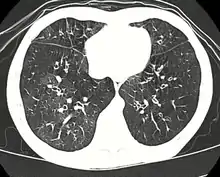

High resolution CT scan showing bronchiolitis obliterans with mosaic attenuation, bronchiectasis, air trapping and bronchial thickening[3]

High-resolution CT scan of a child with post-infectious bronchiolitis obliterans showing glass pattern with air trapping and bronchial thickening

Typically found in young children and is the most common cause at this age.[31] Generally occurs after a viral infection of adenovirus (types 3, 7, and 21), measles (rubeola), mycoplasma, CMV, influenza, and parainfluenza.[4][6] Swyer-James syndrome is a rare complication of bronchiolitis obliterans caused by measles or adenovirus.[32] Post-infectious bronchiolitis obliterans is most common in the southern hemisphere particularly in countries such as Brazil, Argentina, Australia, Chile and New Zealand.[33] There was a large prevalence of the disease in these areas during the 1990s and early 2000s. In one hospital in Buenos Aires, the Ricardo Gutiérrez Children's hospital, the disease accounted for 14% of their inpatient respiratory population from 1993 to 2002.[33] As such, much of the information about post-infectious bronchiolitis obliterans has come from research out of South America. The most significant risk factors for the disease are infection with adenovirus and the need for ventilator support.[33] In contrast with another cause of bronchiolitis obliterans in children, Steven's Johnson's syndrome, post-infectious bronchiolitis obliterans tends to be a chronic but non-progressive disease.[31] The disease can have varying impact on children and their quality of life, which has been studied by lung function tests, as well as their exercise tolerance.[34] Children with lower lung function based on their pulmonary function testing, have lower exercise tolerance, which compounds the impact of the disease on cardiovascular function as they are not able to maintain age appropriate aerobic fitness.[34] This ultimately affects their activities of daily living (ADLs) and their quality of life going forward.[34]

Medical imaging

Early in the disease chest radiography is typically normal but may show hyperinflation.[6] As the disease progresses a reticular pattern with thickening of airway walls may be present.[4][6] HRCT can also show air trapping when the person being scanned breathes out completely; it can also show thickening in the airway and haziness in the lungs.[11] A common finding on HRCT is patchy areas of decreased lung density, signifying reduced vascular caliber and air trapping. This pattern is often described as a "mosaic pattern", and may indicate bronchiolitis obliterans.[6]